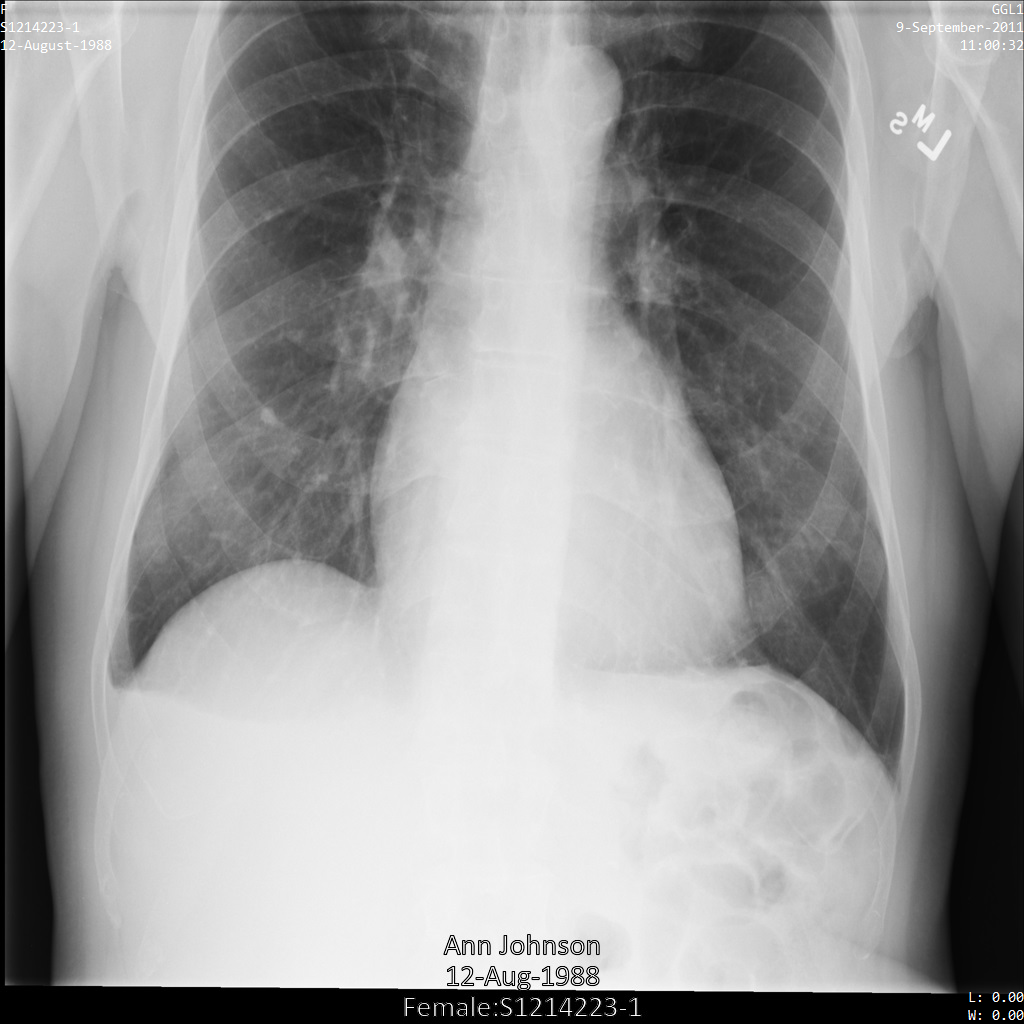

以下各部分提供的示例展示了如何使用各种方法对 DICOM 数据进行去标识化。每个示例都会提供去标识化后的图片输出。每个示例都使用以下原始图片作为其输入:

您可以将每个去标识化操作的输出图片与该原始图片进行比较,以查看该操作的效果。

将图片提交到 Cloud Healthcare API 后,图片显示如下。虽然图片顶部角落显示的元数据已被遮盖,但图片底部的烧屏受保护健康信息 (PHI) 仍然保留。如需一并移除烧屏文字,请参阅遮盖图片中的烧屏文字。

将图片提交到 Cloud Healthcare API 后,图片显示如下。除了 removelist 中提供的标记之外,便只有 PatientBirthDate 会从图片中移除,因为它是 removelist 中唯一与图片中可见的元数据对应的标记。

虽然图片顶部角落的 PatientBirthDate 已根据 removelist 中的配置进行了遮盖,但图片底部的烧屏 PHI 仍会保留。如需一并移除烧屏文字,请参阅遮盖图片中的烧屏文字。

使用 ATTRIBUTE_CONFIDENTIALITY_BASIC_PROFILE 标记过滤条件配置文件将图片提交到 Cloud Healthcare API 后,图片显示如下。虽然图片顶部角落显示的元数据已被遮盖,但图片底部的烧屏 PHI 仍会保留。如需一并移除烧屏文字,请参阅遮盖图片中的烧屏文字。